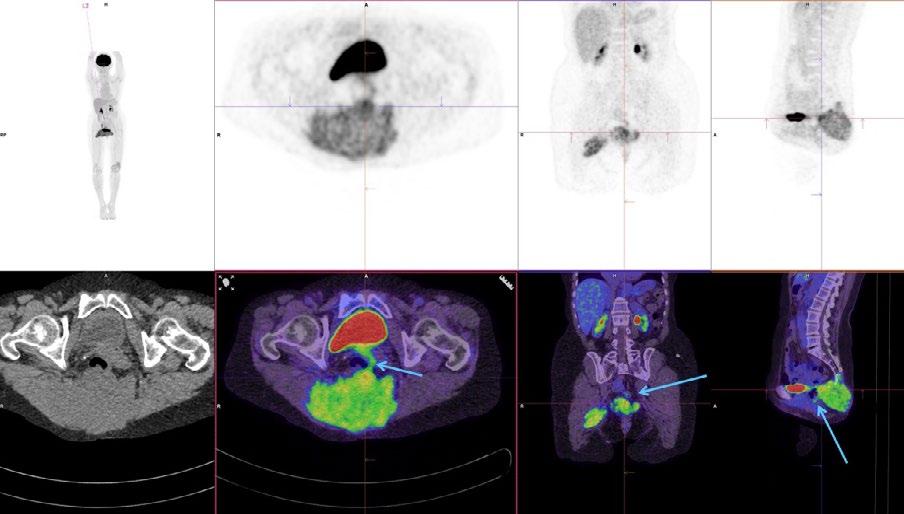

Issuu converts static files into: digital portfolios, online yearbooks, online catalogs, digital photo albums and more. Sign up and create your flipbook.